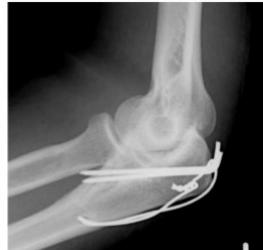

| Tension-band Wires | Indications: Patellar and olecranon fractures, possible in malleolar fractures. Application involves K-wires as a base. | , , , , ![]() |